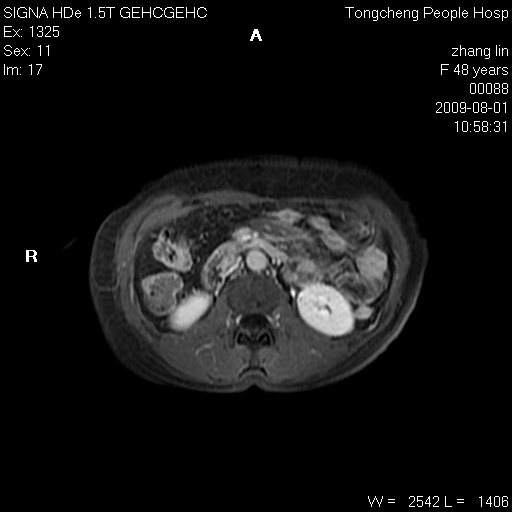

女,48岁。健康体检,彩超发现右肾占位性病变。平素健康。

临床诊断:右肾占位性病变,性质待定(囊肿?肿瘤?)。

上中腹部mr平扫+增强扫描,图像如下:

右肾上极见一类圆形病灶,t1wi呈等信号t2wi呈等高混杂信号,三期增强无强化,边界清---考虑囊肿出血。

同反相位均表现为等信号,病变无强化,考虑含蛋白的囊肿可能,弥散加权相或许有些帮助,

慢性胆囊炎